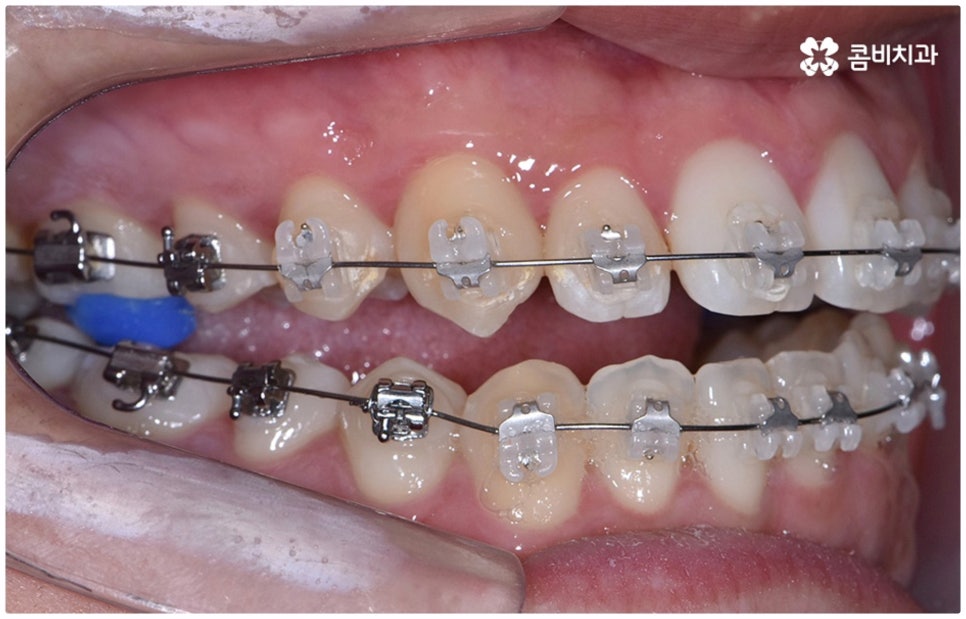

물론 교정 치료에 적기가 정해져 있는 것은 아니기 때문에 성인 이후 중장년 환자분들이라도 교정 치료가 불가능하지는 않으며 상황에 따라 비수술적인 방법으로도 얼마든지 불편함을 줄일 수 있는 경우가 있으니 정확하게 진단한 후 각자에게 맞는 교정 계획을 세워 무리하지 않게 치료를 진행하시길 바라고 있어요. 특히 턱관절과 관련된 부분을 개선하기 위해서는 양악 수술 밖에 방법이 없는 것이 아닌가 생각하셨던 분들이라면 먼저 치과에 내원하셔서 검진과 상담부터 진행해 보시면 마음의 부담을 덜 수 있어 좋을 거예요. 부정교합 3급 치열 (절단교합과 일부 반대교합이 병행되어 있음) 을 가지고 있는 성인분도 교정 치료를 통해 훨씬 자연스럽게 개선이 가능할 수 있으며, 관련 기술 개발 및 미니스크류 등 여러 장치의 발전을 통해 예전에는 적용이 어려웠던 케이스들도 이제는 교정 치료의 도움을 받을 수 있습니다.

치료 계획을 세울 때는 3D CT 같은 정밀 검진 기계를 통해 부정 교합의 정도 및 상하악 관계, 잇몸 건강 상태 등을 꼼꼼하게 살펴보고 회복력과 진행 속도에 영향을 주는 연령, 생활 습관, 평소에 앓고 있는 질환은 없는지 등도 모두 고려하여 세밀한 맞춤 플랜을 세워야 하며 같은 주걱턱 증상이라도 심각한 정도와 턱의 모양에 따라 교정 방법이 달라질 수 있는 만큼 다양한 케이스를 다뤄본 임상 경험을 바탕으로 높은 기술력을 가지고 있는 의료진에게 교정 치료를 받는 것이 굉장히 중요한 포인트라고 할 수 있어요. 정밀 검진 장비 보유 여부, 술자의 뛰어난 숙련도와 함께 체계적인 교정 시스템을 갖추고 사후 관리를 철저하게 해 주는 치과에서 처음부터 끝까지 무리하지 않게 치료를 받는 것도 중요하니 이런 부분도 체크해 보시길 권유드리고 있습니다.

위 사진은 이해를 돕기 위한 이미지이며, 환자의 동의하에 진행되었습니다.

전체 치료 기간은 약 18개월이 소요되었으며,